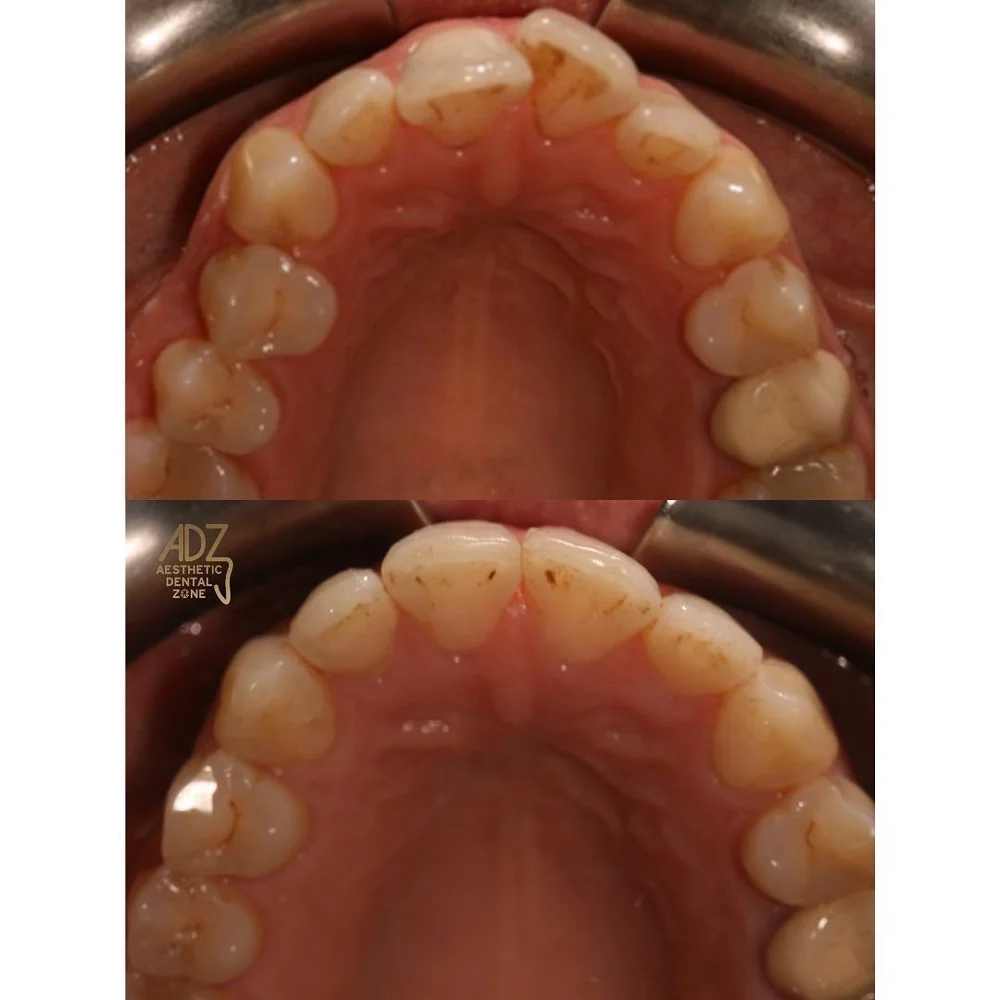

Invisalign treatment is the simple and invisible cosmetic solution to achieving the smile you desire. Avoid fixed appliances (braces) and realign your teeth with a set of our aligners.

Invisalign is an orthodontic treatment that straightens teeth using a system of clear plastic aligners fitted to the patient’s evolving bite. The clear aligners exert force on crooked teeth, gradually shifting them. Patients will be advised to change aligners every one to two weeks as the bite progresses toward an ideal outcome. The numbers of aligners needed is different for each individual.

On the day of the Invisalign fitting appointment. The dentist may cement small handle-like attachments to the teeth; these help the aligners exert proper force on problem areas.  Patients will be asked to see the dentist between 4-6 weeks to see make sure everything is okay and they are happy with the progress.